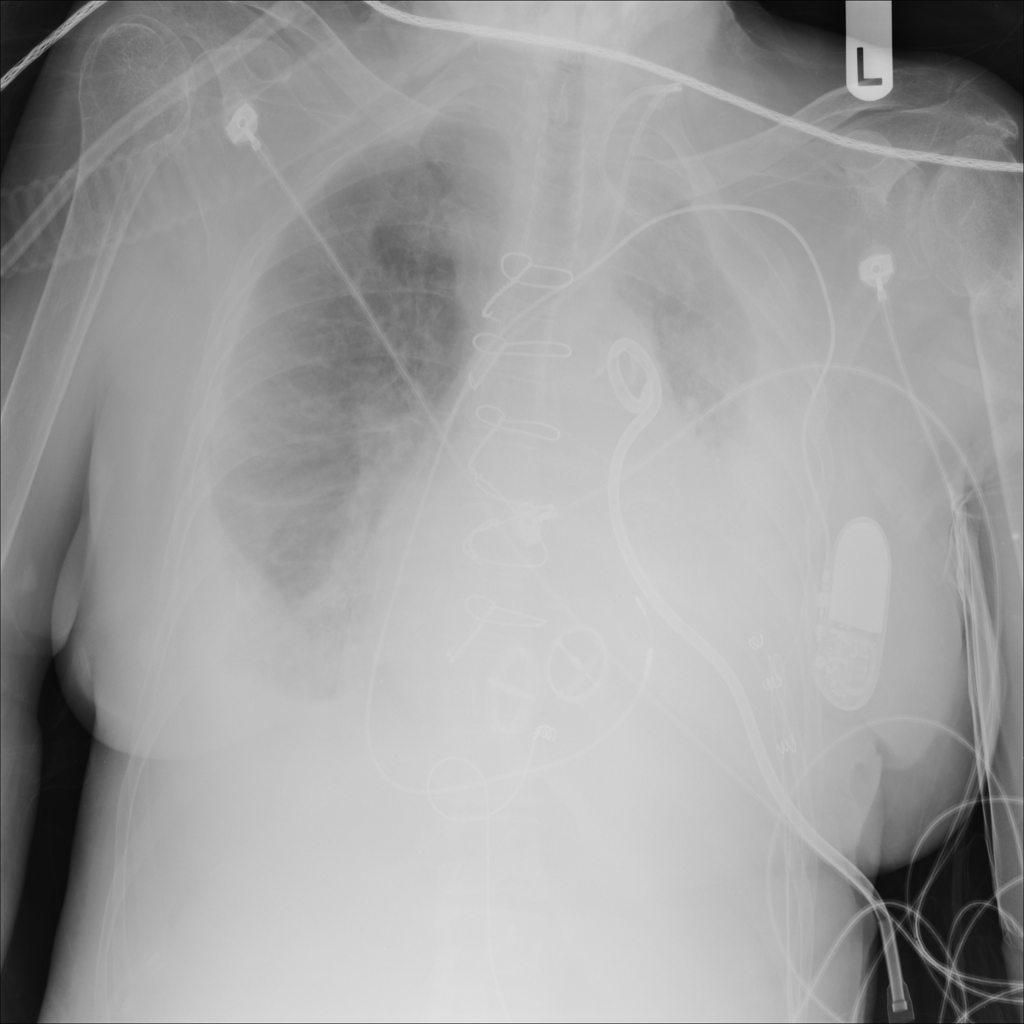

Pleural Effusion

Pleural effusion means extra fluid has collected around the lung in the pleural space. It can happen with heart problems, infection, inflammation, or other underlying conditions.

Showing up to 90 reference images for Effusion.

PAT-40F9 · IMG-004Effusion

PAT-40F9 · IMG-004

PA